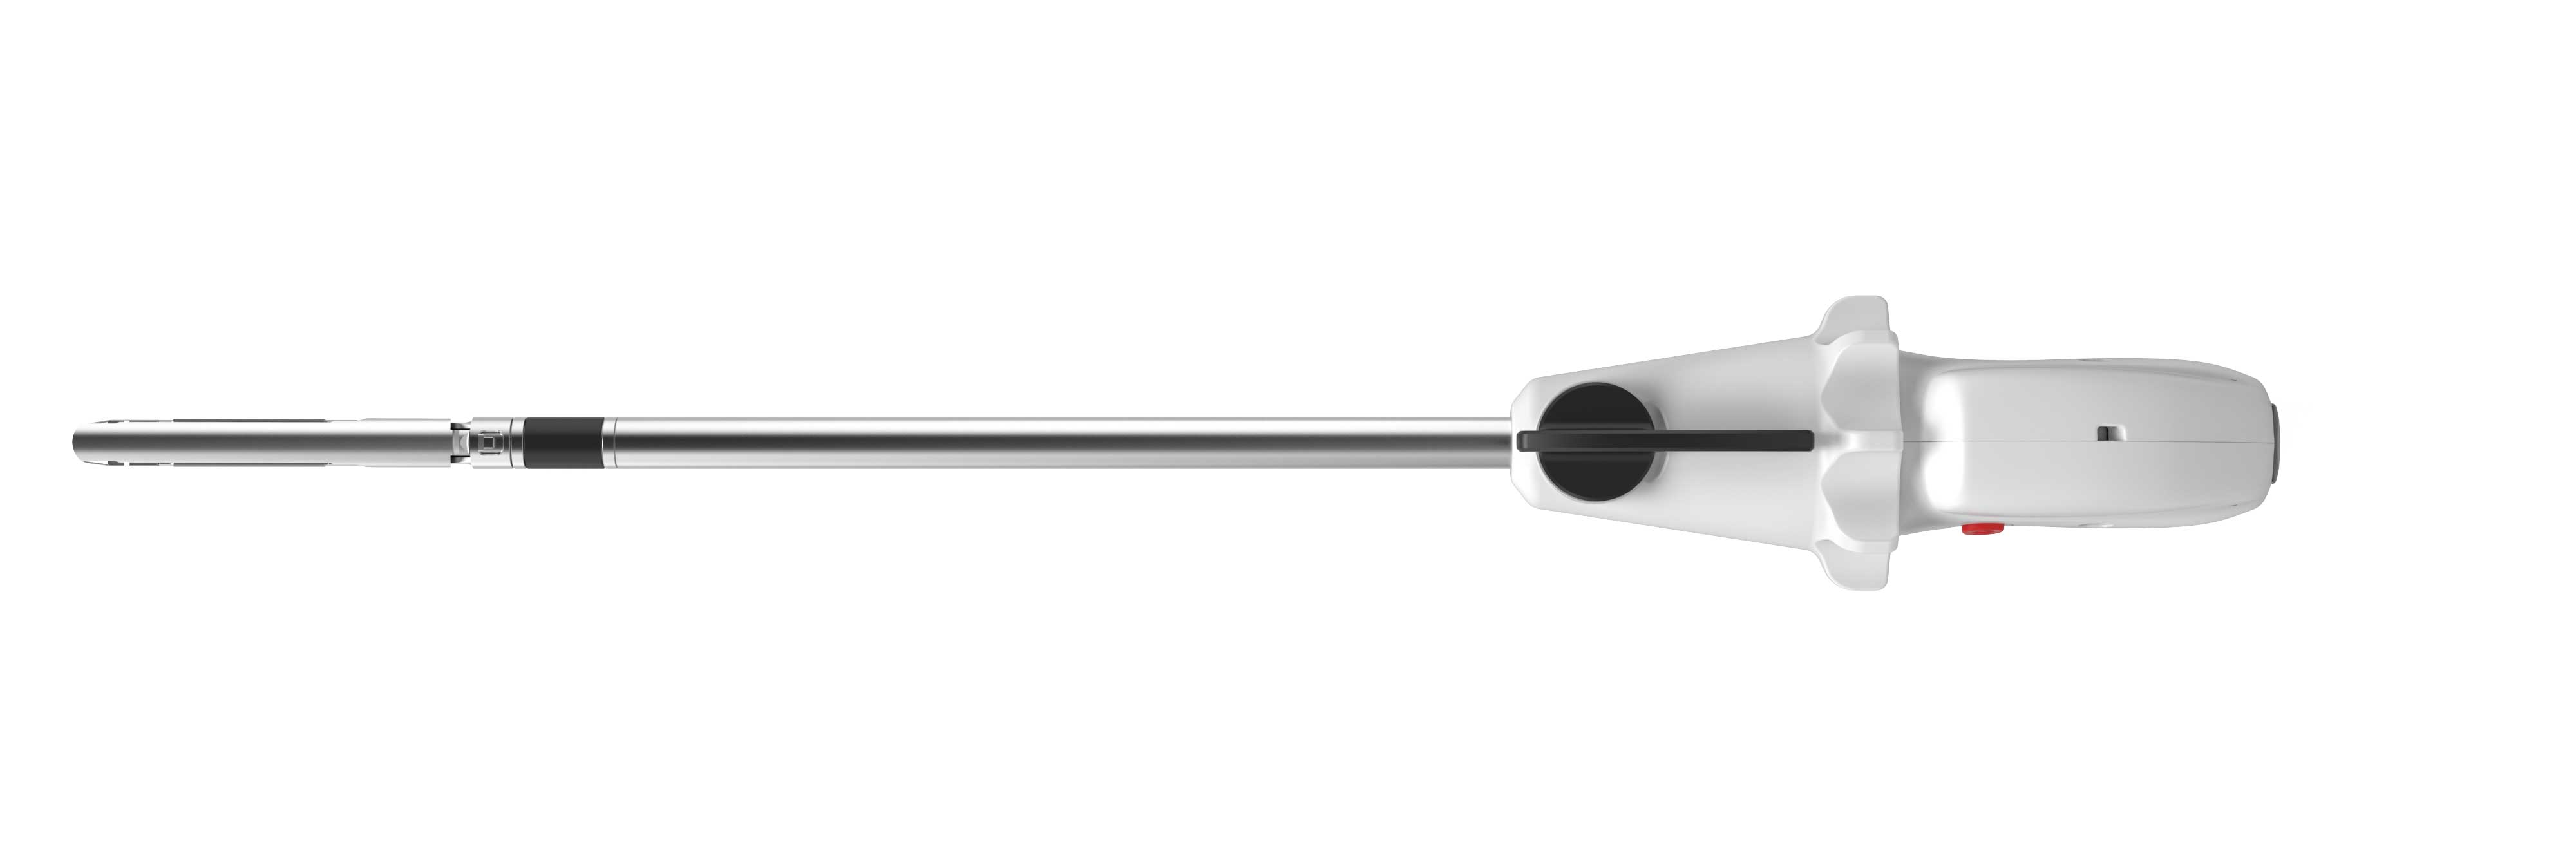

握持轻松,便于施力,更适合东方人和女性术者

自由角度调节,可形成大角度操作维度,适用于狭窄的手术操作部位

率先推出关节无级转弯技术

钳口打开和关闭时,均可实现转弯,操作自由

旋钮键调节角度,简单易懂

产品名称:一次性使用腔镜切割吻合器及组件